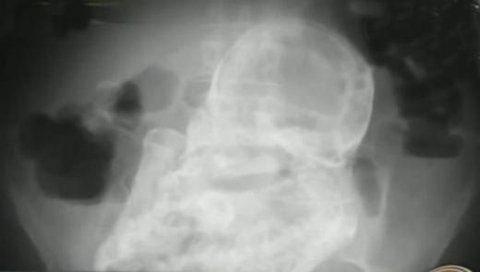

할머니를 진단한 의사는 “초음파검사에선 나오지 않았지만

엑스레이에선 죽은 태아의 얼굴, 팔, 다리, 척추와 갈비뼈 등이

비교적 선명하게 보였다”고 말했다

발달 상태를 볼 때 태아는 임신 20~28주 사이 사망한 것으로 추정된다고 덧붙였다